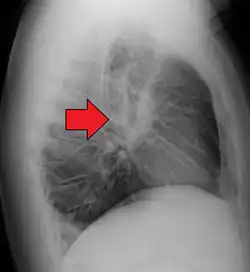

-

Hilar adenopathy especially on the person's left (lateral CXR) -